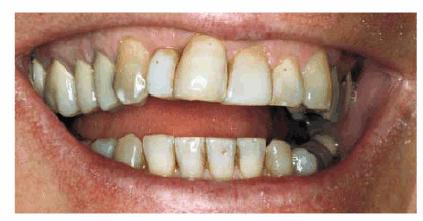

Age and dysfunctional habits can contribute to severe wear over the years. Figures 29-10A, and 29-10B demonstrate evidence of bruxism in an 86-year-old

woman who had been advised to wear a bite guard when she was in her mid 50s.

She disappeared from the practice and returned 30 years later demonstrating

severe wear, loss of vertical dimension, loss of masticatory function, and

temporomandibular pain. More importantly, she was embarrassed by her smile. Her

treatment plan consisted of a temporary crown and bridge to restore vertical

dimension and comfort. She was subsequently treated months later with fixed prosthodontics

using metal-ceramic restorations (Figure 29-10C). She regained much of her self-confidence, as

well as masticatory function, following the esthetic reconstruction of the

maxillary arch (Figure 29-10D) and planned to restore the lower arch.

Figure 29-10A: This lady presented with a severe bruxism habit that resulted in virtually all of her maxillary teeth being hidden when she smiled.

Figure 29-10B: Although she was advised more than 30 years previously to wear a night guard, she chose not to do so.

Figure 29-10C: Crown lengthening followed by prosthodontic reconstruction helped to recreate her smile. The next step is for her to rebuild the mandibular arch.

Figure 29-10D: The reconstructed teeth of this 88-year-old lady now enhance her smile.